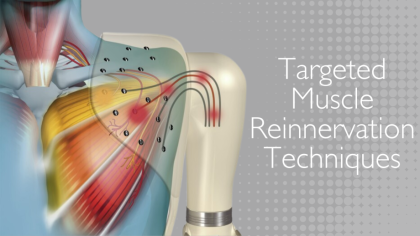

Read MoreEnhancing Prosthetic Functionality with Advanced Targeted Muscle Reinnervation (TMR) Techniques

Discover how Targeted Muscle Reinnervation (TMR) surgery enhances prosthetic functionality and manages neuroma pain for amputees. Learn about advanced techniques, see illustrative resources, and explore the integration of VR technology at our internationally recognized Amputee Clinic